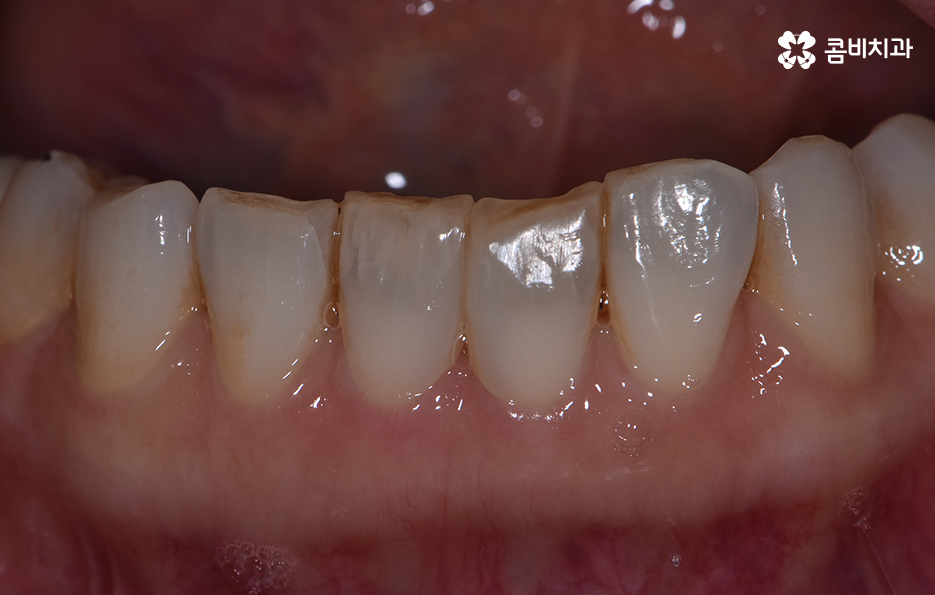

위 환자분의 경우 블랙트라이앵글 레진으로 치료를 하였는데

이러한 레진 치료의 장점은 빠르게 심미성을

회복할 수 있다는 점이며 비교적 저렴하다는 장점이 있습니다.

보다 심미적인 치료를 위해서 치간 삭제를 통해서

라미네이트나 올세라믹과 같은 치료 방법이 활용되기도 합니다.

라미네이트의 경우 심미적으로 우수한 효과를

빠르게 낸다는 장점과 함께 치아 삭제에

대한 부담이 다소 있을 수 있습니다.